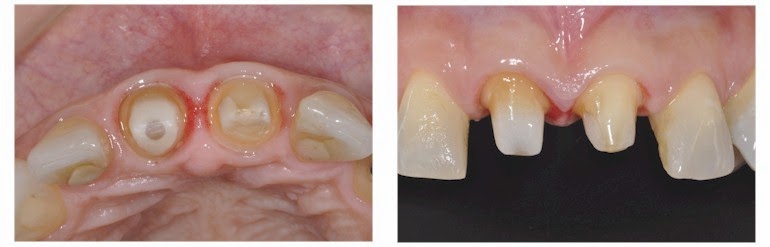

Restauraciones De Dientes Severamente Destruidos

es.slideshare.net